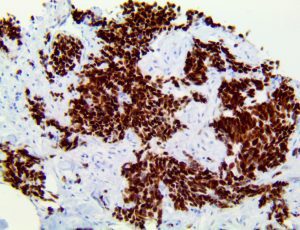

It is the ICU physician who is most likely to witness one of the deadliest manifestations of the abnormal immunological response, the cytokine storm syndrome (CSS). This response is also referred to by some as the cytokine release syndrome (CRS). CSS is characterized by continuous activation and expansion of macrophage and lymphocyte populations, which secrete large amounts of cytokines, causing the cytokine storm. This massive cytokine release is akin to hemophagocytic lymphohistiocytosis (HLH) disease, a syndrome characterized by initial unchecked and persistent activation of cytotoxic T lymphocytes and NK cells.

Clinical and laboratory manifestations of HLH include fever, enlarged liver and/or spleen, neurologic dysfunction, coagulopathy, liver dysfunction, cytopenias (i.e., low levels of erythrocytes, leukocytes, and/or platelets), hypertriglyceridemia, hyperferritinemia, hemophagocytosis, and eventually diminished NK cell activity as the immune system becomes progressively paralyzed. HLH can be familial (primary HLH) or secondary to another disease process (sHLH), such as rheumatic disease, in which it is referred to as macrophage activation syndrome (MAS, characterized by elevated ferritin).